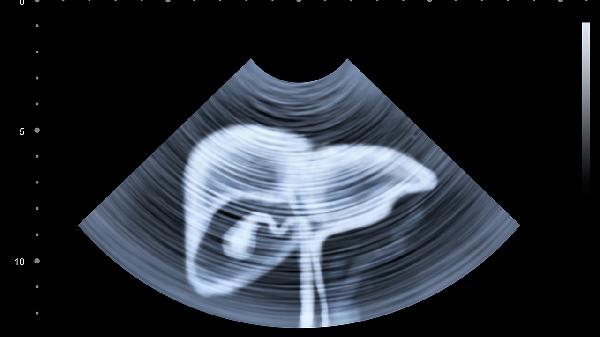

乙肝/丙肝携带者、长期饮酒者、脂肪肝患者应每6个月做一次肝脏超声和甲胎蛋白检查。